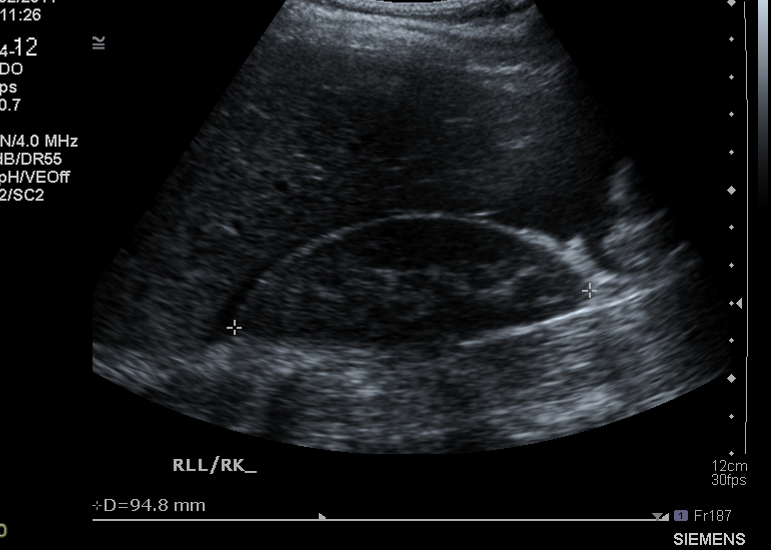

What pathological sign is shown in this pic ?

Ascities in the hepatorenal recess due to an inflam reaction in the peritoneum

What type of mass is shown

Cyst becaue there is mainly fluid in it - i.e. black filled